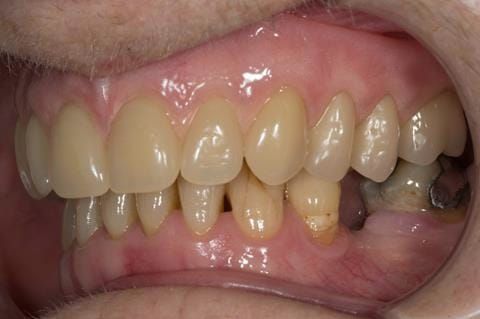

- Poorly fitting cobalt chromium based maxillary partial denture, which has been added to. This exhibited poor retention, stability and tissue fit (support). Unable to wear a new acrylic based denture.

- Eight mandibular anterior teeth worn incisal edges from now extracted maxillary anterior crowns. Gingivitis - owing to inadequate oral hygiene.

- Bruxism.